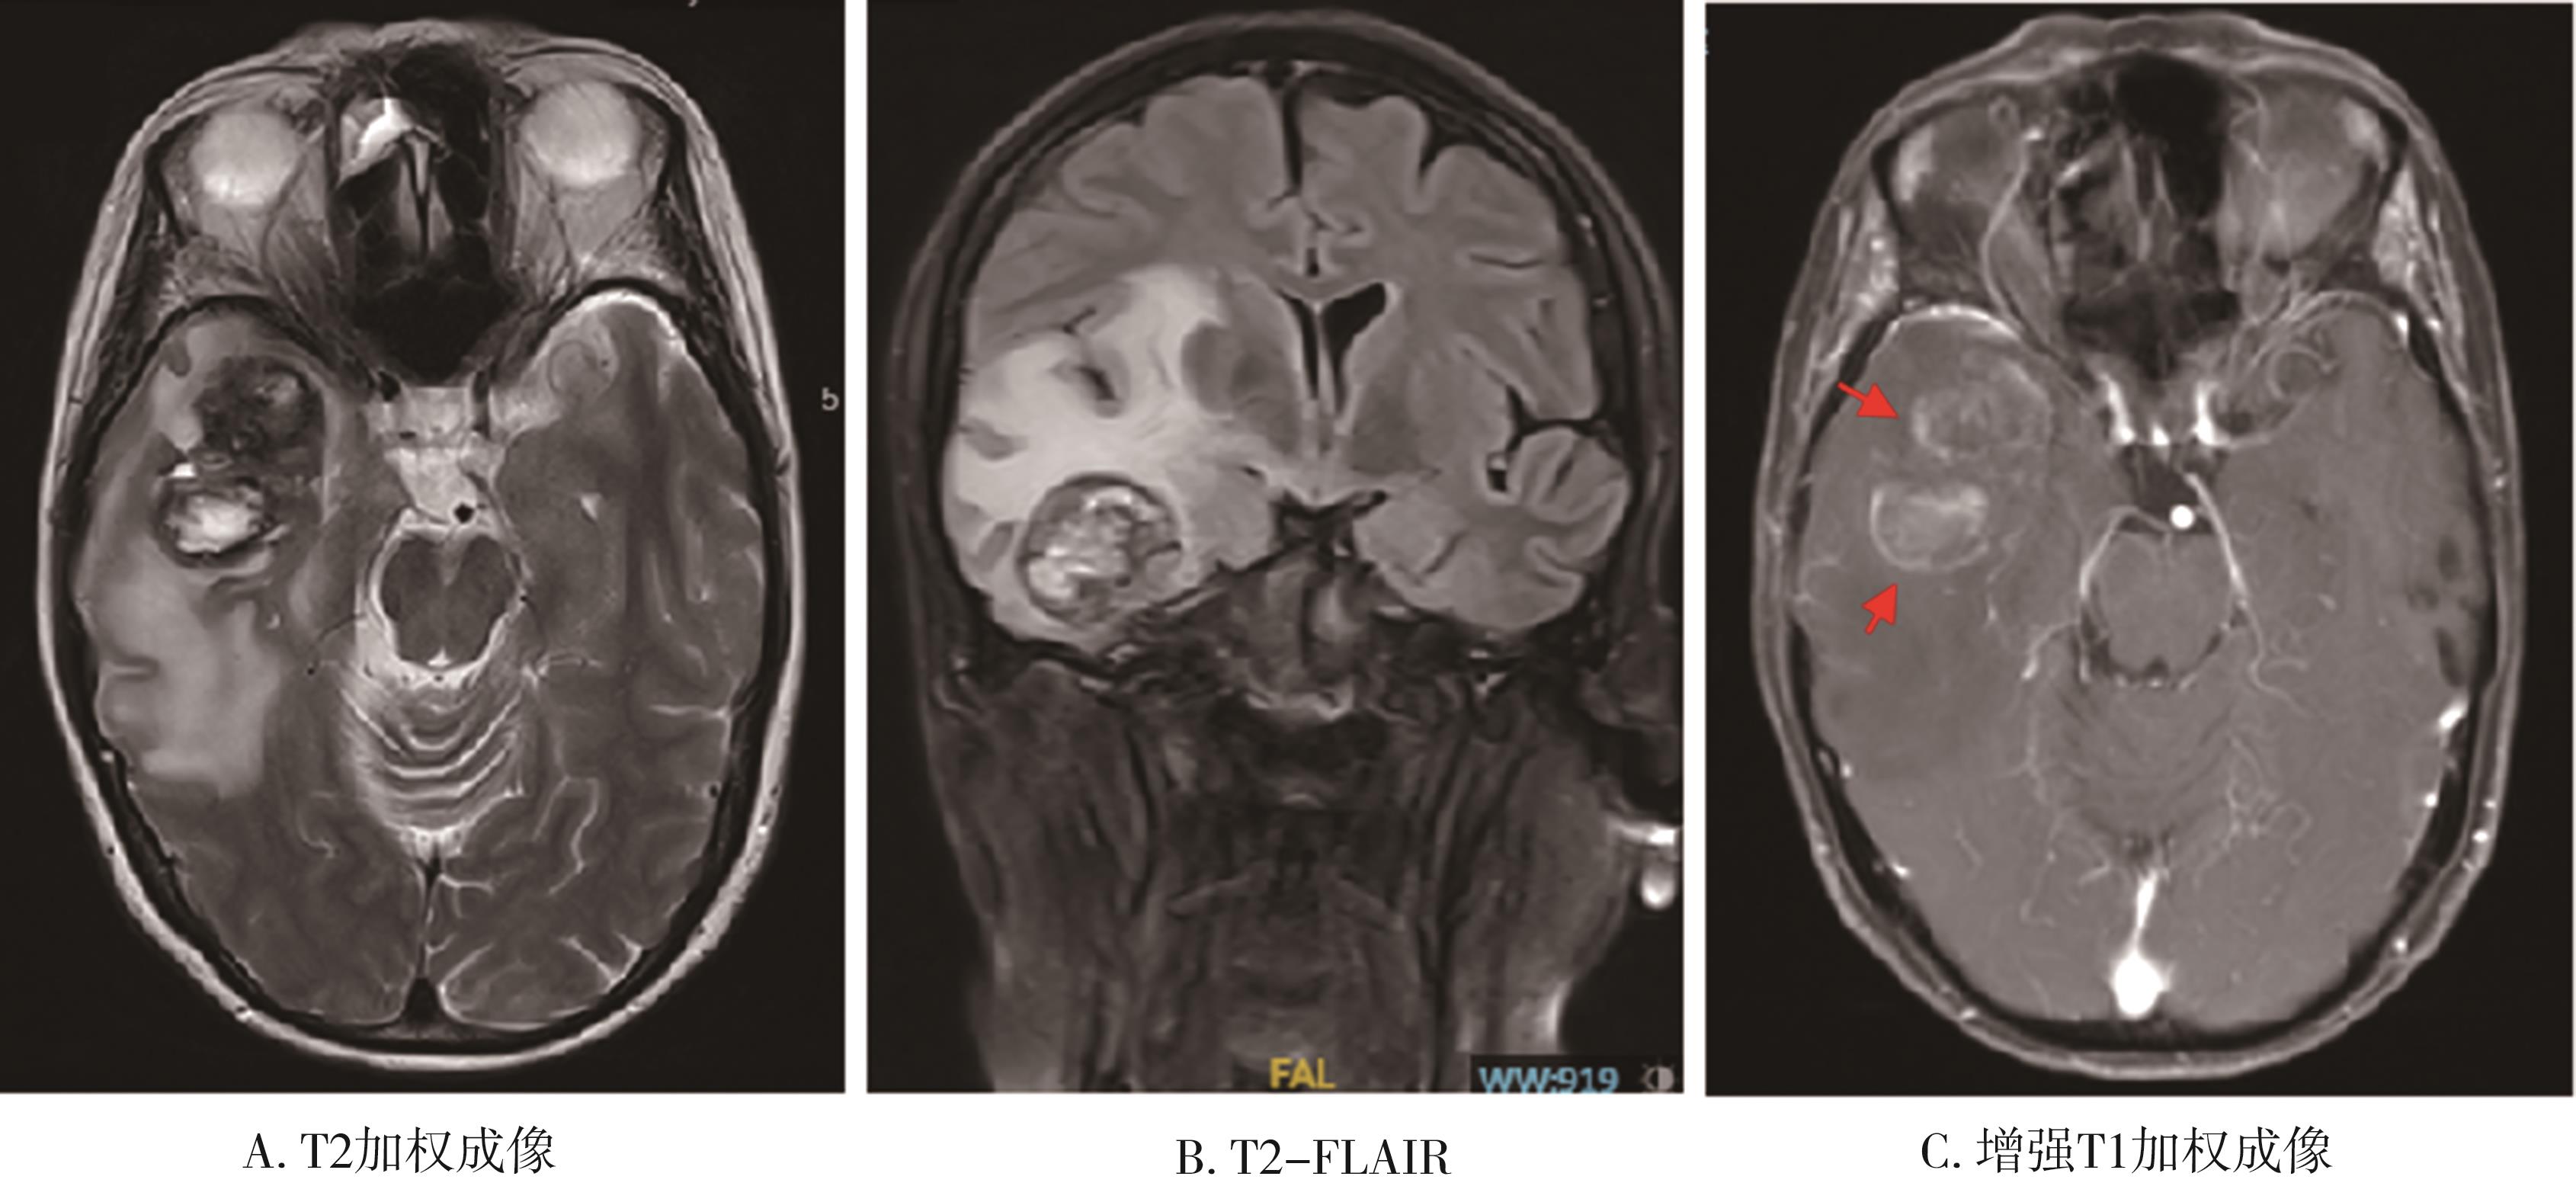

• 放射性脑损伤的治疗进展

摘要:放射治疗在控制头颈部肿瘤提高患者生存率的同时,对周围正常脑组织也造成不同程度的损伤,引起放射性脑坏死和认知功能下降,其发生率最高可达90%,严重影响患者的生活质量。研究人员近年来在多个层面上对放射性脑损伤的潜在病因进行了探索,通过筛查和鉴定不同干预靶点,为预防和治疗放射性损伤提供了新的策略。本文对放射性脑损伤的发生发展机制进行了综述,并回顾了现有的药物及非药物干预手段,提出了目前该领域面临的挑战及未来的研究方向。